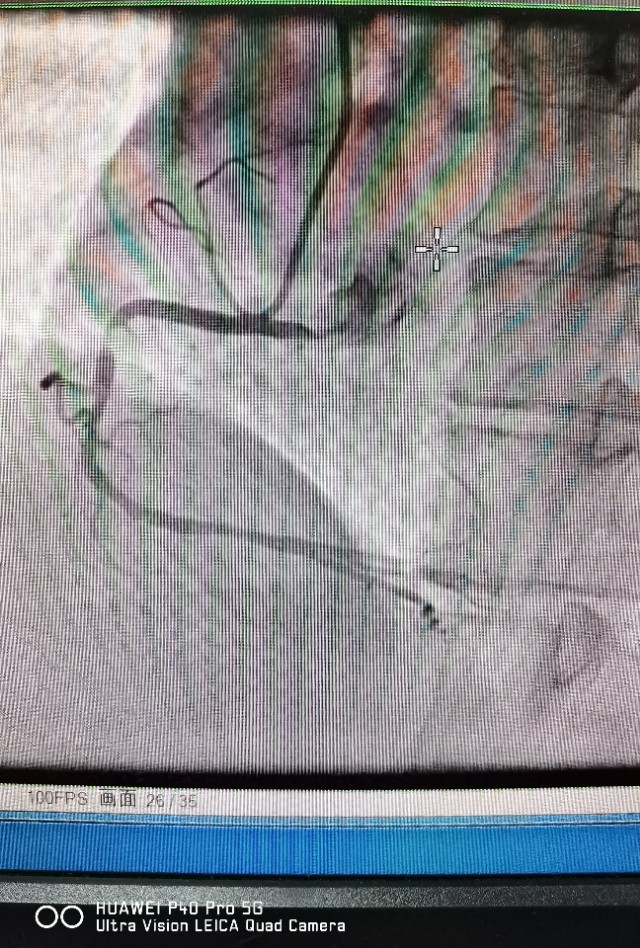

病例2 及时发现ACS斑块,避免心肌梗死发生

中年男性,反复不稳定心绞痛发作,冠脉CTA提示中重度病变,造影发现RCA弥漫病变,OCT发现冠脉内红色,白色血栓形成,随时可能发生心肌梗死!

植入支架后恢复良好,患者胸痛症状消失!